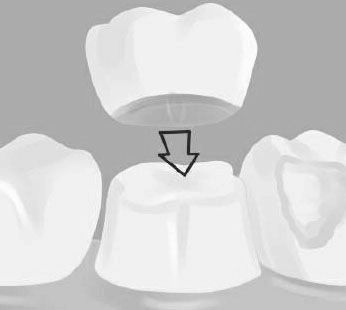

Болить зуб під коронкою. Причини.

Причин болю під коронкою зуба може бути кілька, розглянемо найбільш поширені з них:

Погане прилягання коронки до зуба

Також трапляються випадки неякісної або відверто поганий підгонки коронки до зуба. В результаті чого простір між зубом і коронкою не піддається чищенню, туди потрапляють частинки їжі і викликають розмноження мікроорганізмів.